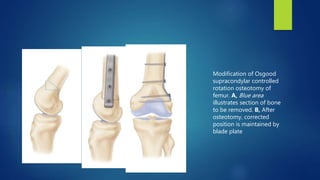

Modification of Osgood

supracondylar controlled

rotation osteotomy of

femur. A, Blue area

illustrates section of bone

to be removed. B, After

osteotomy, corrected

position is maintained by

blade plate

Modification of Osgood supracondylarcontrolled rotation osteotomy of femur. A, Blue area illustrates section of bone to be removed. B, After osteotomy, corrected position is maintained by blade plate